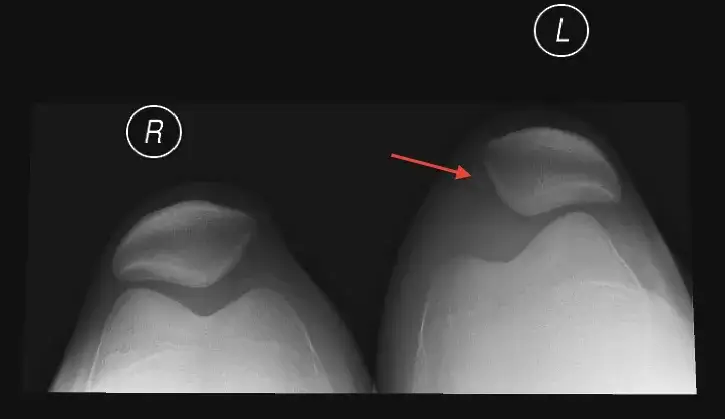

Leczenie operacyjne, takie jak rekonstrukcja więzadła rzepkowo-udowego przyśrodkowego (MPFL), jest rozważane w sytuacjach, gdy mamy do czynienia z nawykowym zwichaniem rzepki, dużą niestabilnością stawu lub poważnymi uszkodzeniami towarzyszącymi. Po operacji okres unieruchomienia i chodzenia o kulach trwa zazwyczaj około 3-4 tygodni. Powrót do normalnego funkcjonowania zajmuje około 2 miesięcy, natomiast do pełnej aktywności sportowej około 6 miesięcy. Chociaż rehabilitacja po operacji jest często dłuższa, bywa bardziej ustrukturyzowana i ma na celu długoterminową stabilizację kolana.

Niestety, dla niektórych osób zwichnięcie rzepki nie jest jednorazowym incydentem. Nawykowe zwichnięcie rzepki to sytuacja, w której rzepka zwicha się wielokrotnie, często przy niewielkich urazach, a nawet podczas codziennych czynności. Dzieje się tak zazwyczaj z powodu utrzymującej się niestabilności, często wynikającej z predyspozycji anatomicznych (np. dysplazja bloczka udowego, koślawość kolan) lub niewystarczającej rehabilitacji po pierwszym urazie. Pierwsze sygnały ostrzegawcze to poczucie niestabilności, "uciekania" rzepki, a także powtarzające się epizody bólu i obrzęku, nawet po niewielkim wysiłku.

Jeśli mimo sumiennej rehabilitacji i przestrzegania zaleceń, problem nawraca, leczenie zachowawcze może okazać się niewystarczające. W takich sytuacjach, zwłaszcza gdy zwichnięcia są częste, bolesne i znacząco wpływają na jakość życia, konieczne jest rozważenie leczenia operacyjnego. Najczęściej wykonywaną procedurą jest rekonstrukcja więzadła rzepkowo-udowego przyśrodkowego (MPFL), które jest głównym stabilizatorem rzepki. Operacja ma na celu przywrócenie anatomicznej stabilności rzepki i zmniejszenie ryzyka kolejnych zwichnięć. Decyzja o zabiegu zawsze podejmowana jest indywidualnie, po dokładnej diagnostyce i konsultacji z ortopedą, uwzględniając stopień niestabilności, predyspozycje anatomiczne oraz Twoje oczekiwania.